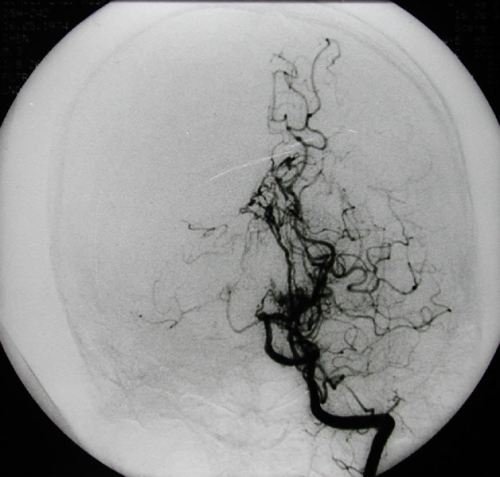

烟雾病又名Moyamoya病,脑底异常血管网,是一组以Willis环双侧主要分支血管(颈内动脉虹吸段及大脑前、中

烟雾病是一种病因不明的、以双侧颈内动脉末端及大脑前动脉、大脑中动脉起始部慢性进行性狭窄或闭塞为特征,